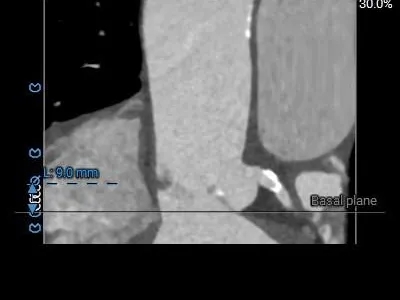

冠脉风险评估

LCA:9mm

RCA:14.8mm

左右窦瓣叶长度均可